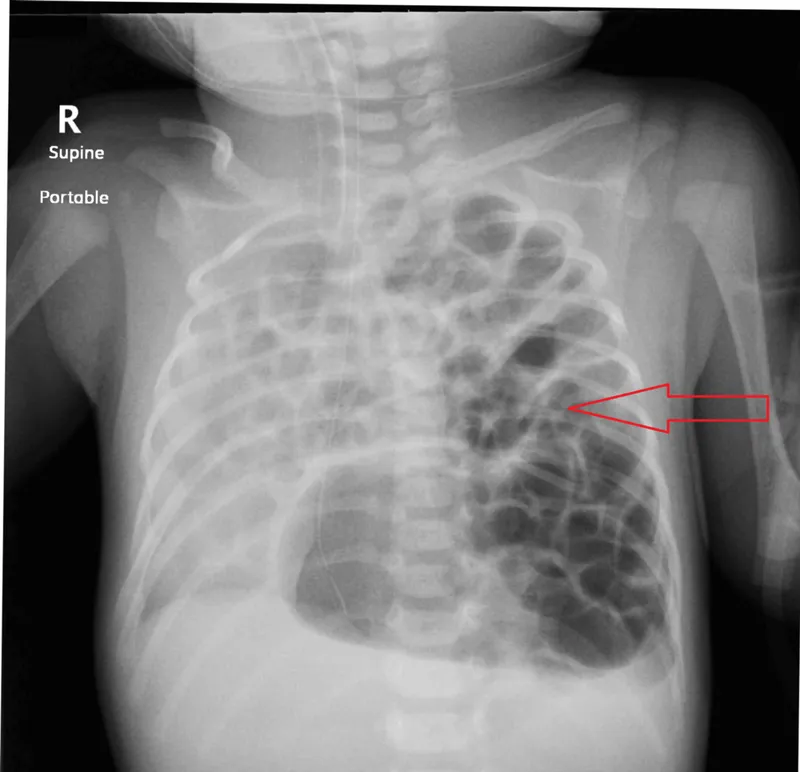

- Postnatal: Resp. distress, scaphoid abdomen, ā breath sounds. CXR confirms.

- Diagnosis: prenatal ultrasound or postnatal chest X-ray showing bowel in thorax.